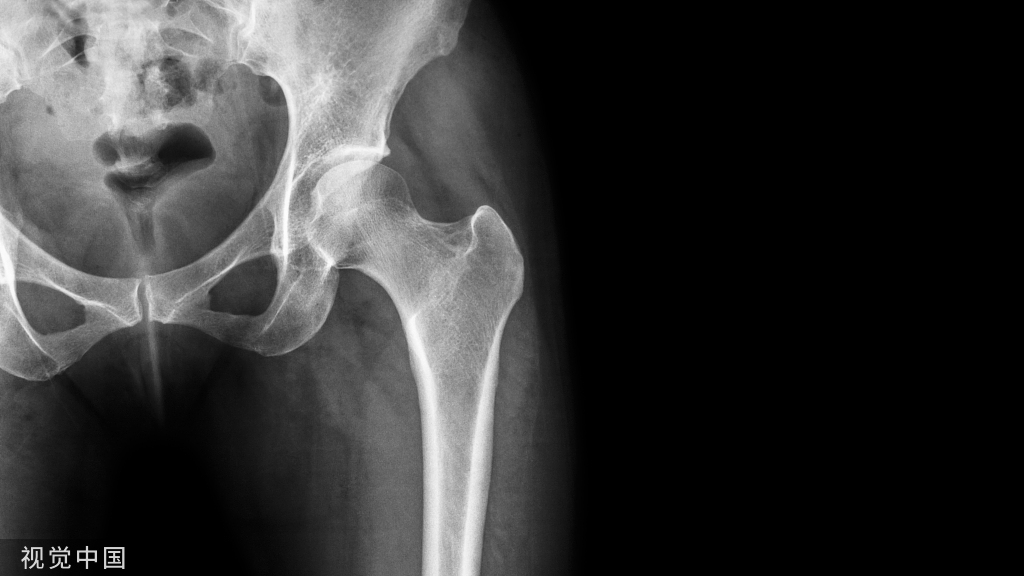

3种情形,不建议取

1.老年人。尤其是有基础病的老年人,且固定物又无明显影响的,通常可以让内固定物留在原处不动。

2.内固定物置于容易发生血管或神经损伤的部位。比如肱骨干、桡骨干、肘前侧、骨盆,这些部位的钢板大多紧邻血管神经,解剖复杂,再加上已经手术过一次,骨折部位周围的肌肉软组织满是瘢痕,解剖层次还不如刚骨折时候清晰。手术损伤血管神经的风险比放内固定物时候还要大,所以尽量不要取。

3.在体内放置时间过长。内固定物在体内放置时间越长,金属钢板和螺钉之间越容易出现问题,加上周围的骨痂已经牢固包绕钢板生长,再加上十几年前上钢板所用的配套器械早已更新换代,这种钢板取起来特别容易出现滑丝、断钉和取钉困难的情况。除非逼不得已,否则不要取。